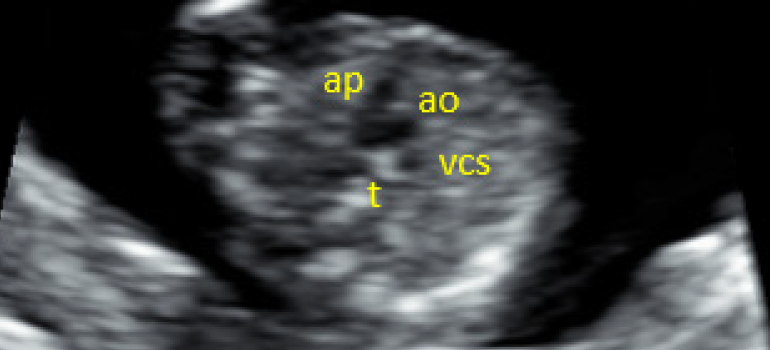

O desenvolvimento das sondas transvaginal e transabdominal de alta frequência e alta resolução juntamente com melhorias substanciais em imagens de ampliação e processamento de sinais aumentaram drasticamente a capacidade de visualização do coração fetal durante o primeiro e o segundo trimestres da gestação, permitindo investigação detalhada da anatomia cardíaca fetal e o diagnóstico de defeitos cardíacos. Atualmente é prática padrão em muitos centros de medicina fetal oferecer ecocardiografia a partir de 11 semanas de gestação.

A ecocardiografia fetal precoce é ferramenta poderosa e confiável para o diagnóstico de cardiopatias congênitas no início da gravidez. Entretanto, em virtude da possibilidade de falha em alguns defeitos significantes, particularmente aqueles que progridem ou evoluem durante a gestação, é recomendado repetir o exame mais tarde na gravidez.